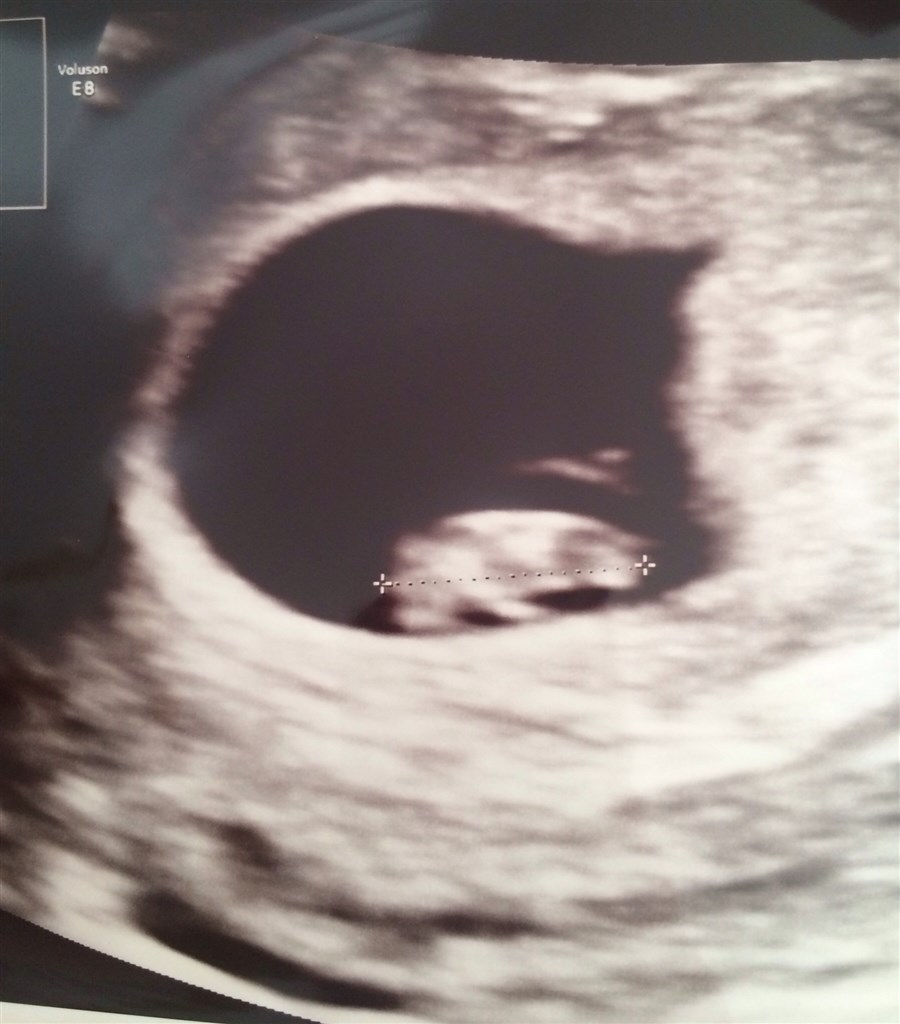

Her er et billed fra selvbetalt scanning igår

vi hørte et fint lille hjerte og blev sat til at være 7+3 (7+4 idag)